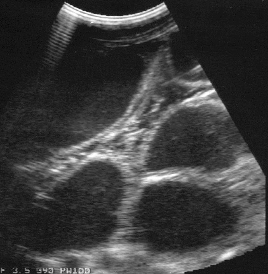

ultrasound: swirling echogenic fluid

presence of distended loops of intestine on rectal exam and ultrasound